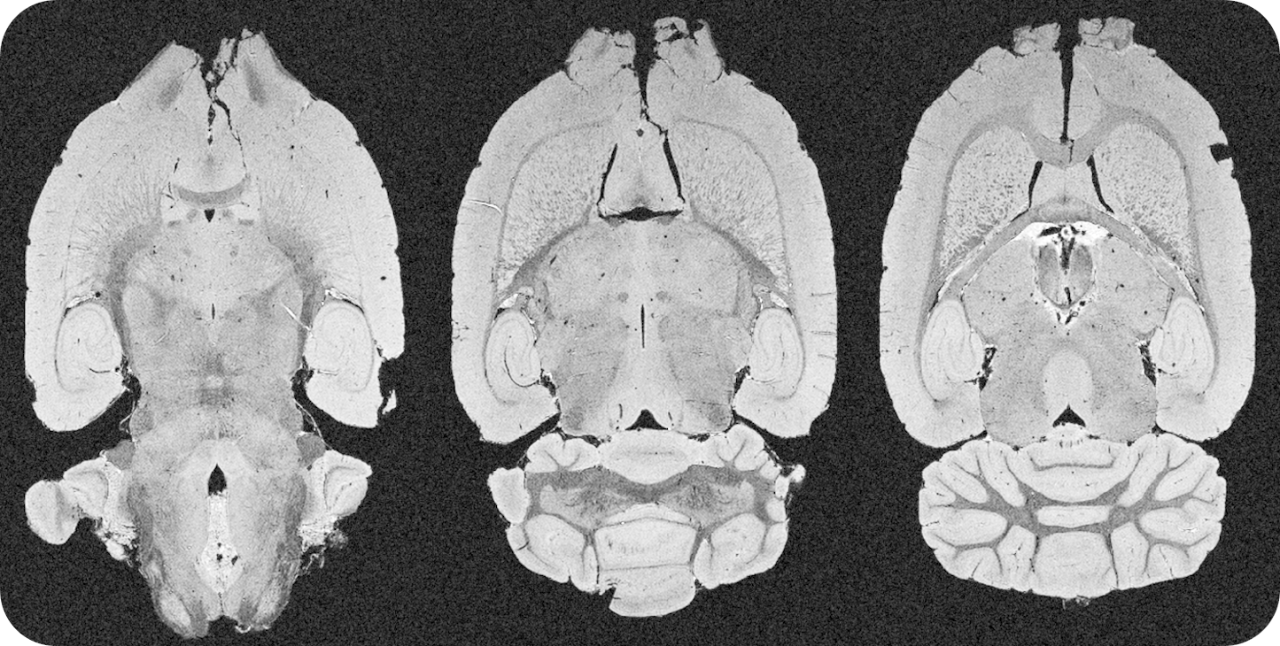

Simplified operation for examinations of mice brain, head, and body

The ultra-high field of the BioSpec 152/11 provides extreme sensitivity for greatest resolution. Its streamlined design for mice studies makes handling simple, while its powerful software guarantees best results. It can be equipped with the MRI CryoProbe to increase sensitivity even further and together with the gradient strength of up to 1000 mT/m, highest resolution is achieved. It is built with nitrogen-free Ultra Shielded and helium Refrigerated (US/R) magnet technology for long service intervals

• Crisp and highly resolved images with native gradient strength of 740 mT/m, upgradable to 1000 mT/m

• Over 100 validated and ready to use in vivo protocols and scan programs for mice and rats